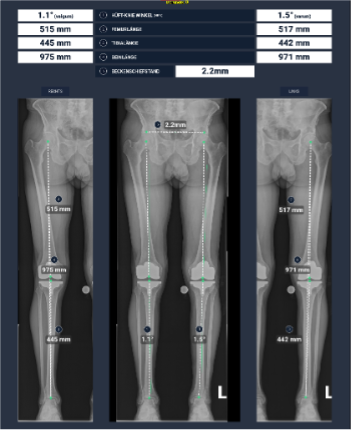

Planungssoftware nach erfolgter CT-Bildgebung zur Anfertigung der PSI (Patientenspezifische Schnittblöcke). Im unteren rechten Bild sind die Schnittblöcke schematisch auf den Oberschenkel – und Unterschenkelknochen positioniert. Mit freundlicher Genehmigung der Fa. Medacta

Beispiel eines Planungsreportes für das «kinematic Alignement» nach CT graphischer Vermessung für die operative Versorgung mit den PSI und postoperative Röntgenkontrolle (Orthoradiogramm und Knie links a.p.-seitlich mit Patella tangential) Aufnahme bei Patellarückflächenersatz